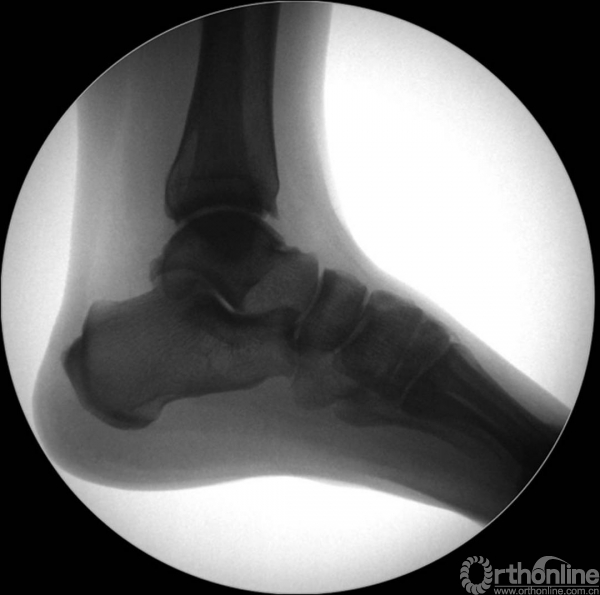

X线诊断:标准的踝关节影像学评估应包括3个位相:前后位(图5),踝穴位(内旋15°)(图6),侧位(图7)。

图7 侧位